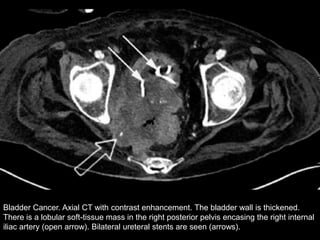

Bladder Cancer. Axial CT with contrast enhancement. The bladder wall is thickened.

There is a lobular soft-tissue mass in the right posterior pelvis encasing the right internal

iliac artery (open arrow). Bilateral ureteral stents are seen (arrows).